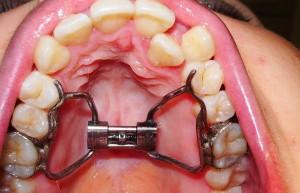

Если места на зубной дуге недостаточно и брекеты не могут гарантировать необходимый эффект, обращаются к аппарату Дерихсвайлера. Он представляет собой дугу с кольцами на концах. Кольца насаживаются на зубы, этим действием аппарат фиксируется. В центре дуги находится винт, который активируется для создания давления на кость.

Небный расширитель

Это усложненный вариант аппарата Дерихсвайера. От центральной раздвигающей части отходит 4 дуги с кольцами, которые закрепляются на задних коренных зубах. Конструкция оказалась очень эффективной в лечении детей: у ребенка увеличение челюсти происходит примерно за три недели. Взрослым потребуется больше времени, вплоть до полутора лет.

Как понятно из названия, небному расширителю под силу только расширение верхней челюсти. Для расширения нижней челюсти придется подбирать другую конструкцию. Иногда данный аппарат путают с небным бюгелем, у которого совершенно другая функция: он служит для фиксации коренных зубов при коррекции прикуса. Часто он играет роль вспомогательной конструкции, например, применяется с брекетами.

Лечение длится 2-3 недели, прогресс можно отмечать по увеличивающемуся расстоянию между фронтальными зубами. После лечения аппарат держат в ротовой полости до 6 месяцев для закрепления результата. На фото ниже видна изначально узкая верхняя зубовая дуга до расширения и после лечения.